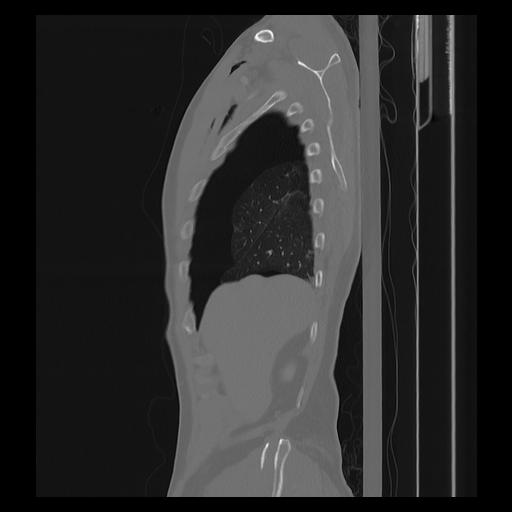

33 PULMON,CE,Sagittal,3.000,PULMON,Sagittal,